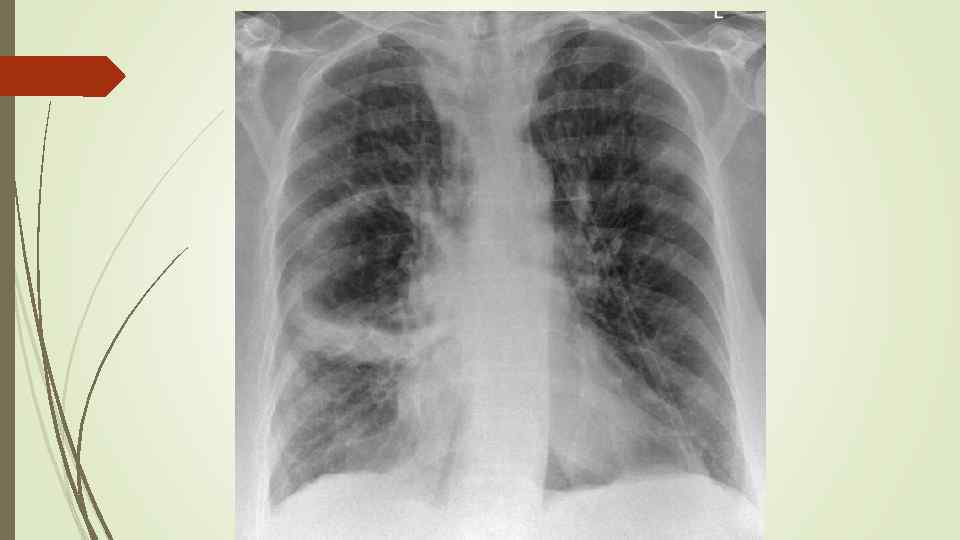

Плевральный выпот Скопление жидкости в плевральной полости (исключение гемоторакс, хилоторакс, пиоторакс) Транссудат Экссудат Плеврит

Плевральный выпот Скопление жидкости в плевральной полости (исключение гемоторакс, хилоторакс, пиоторакс) Транссудат Экссудат Плеврит

Осумкованные плевриты: а) пристеночные (паракостальные) осумкования, прилежащие широким основанием к поверхности ребер; б) верхушечные (апикальные) осумкования; в) диафрагмальные (базальные) осумкования, расположенные между основанием легкого и диафрагмой; г) междолевые (интерлобарные) осумкования, расположеные между долями легких; д) парамедиастинальные осумкования, расположенные в заворотах парамедиастинальной плевры.

Осумкованные плевриты: а) пристеночные (паракостальные) осумкования, прилежащие широким основанием к поверхности ребер; б) верхушечные (апикальные) осумкования; в) диафрагмальные (базальные) осумкования, расположенные между основанием легкого и диафрагмой; г) междолевые (интерлобарные) осумкования, расположеные между долями легких; д) парамедиастинальные осумкования, расположенные в заворотах парамедиастинальной плевры.

Пневмоторакс – скопление газа в плевральной полости, ведущее к спадению ткани легкого, смещению средостения в здоровую сторону, сдавлению кровеносных сосудов, опущению купола диафрагмы, что, в конечном итоге вызывает расстройство функции дыхания и кровообращения. Различают травматический, спонтанный и ятрогенный пневмоторакс. В зависимости от наличия связи с окружающей средой различают закрытый, открытый и клапанный пневмоторакс.

Пневмоторакс – скопление газа в плевральной полости, ведущее к спадению ткани легкого, смещению средостения в здоровую сторону, сдавлению кровеносных сосудов, опущению купола диафрагмы, что, в конечном итоге вызывает расстройство функции дыхания и кровообращения. Различают травматический, спонтанный и ятрогенный пневмоторакс. В зависимости от наличия связи с окружающей средой различают закрытый, открытый и клапанный пневмоторакс.

Рентгенологическое исследование: свободный газ в плевральной полости (участок просветления, лишенный легочного рисунка, расположенный на периферии легочного поля, на фоне пневмоторакса отчетливее, чем обычно, видны детали костного скелета грудной клетки) поджатое лёгкое, степень спадения которого зависит от величины пневмоторакса при напряжённом пневмотораксе средостение смещается в здоровую сторону.

Рентгенологическое исследование: свободный газ в плевральной полости (участок просветления, лишенный легочного рисунка, расположенный на периферии легочного поля, на фоне пневмоторакса отчетливее, чем обычно, видны детали костного скелета грудной клетки) поджатое лёгкое, степень спадения которого зависит от величины пневмоторакса при напряжённом пневмотораксе средостение смещается в здоровую сторону.

Гидропневмоторакс имеет такие же причины возникновения и рентгенологические проявления, как и пневмоторакс, но в плевральной полости помимо воздуха находится жидкость. Рентгенологически помимо общих признаков с пневмотораксом появляются дополнительные: - затемнение высокой интенсивности и однородной структуры, нижняя граница которого сливается с диафрагмой, а верхняя при вертикальном положении образует горизонтальный уровень; - средостение резко смещено в противоположную сторону.

Гидропневмоторакс имеет такие же причины возникновения и рентгенологические проявления, как и пневмоторакс, но в плевральной полости помимо воздуха находится жидкость. Рентгенологически помимо общих признаков с пневмотораксом появляются дополнительные: - затемнение высокой интенсивности и однородной структуры, нижняя граница которого сливается с диафрагмой, а верхняя при вертикальном положении образует горизонтальный уровень; - средостение резко смещено в противоположную сторону.